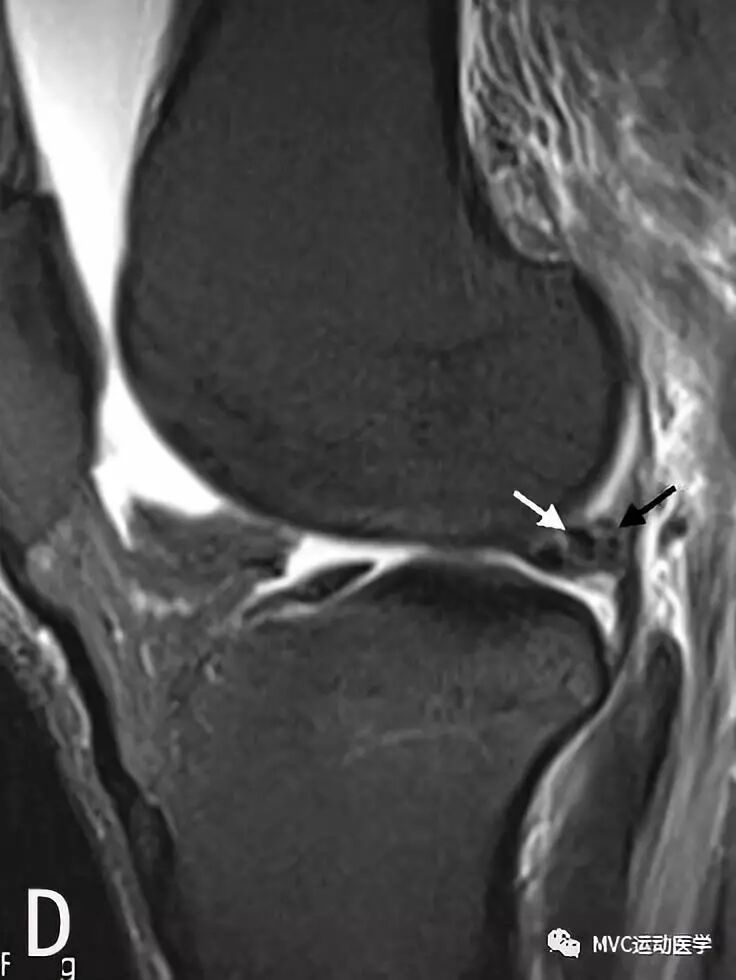

横韧带是连接内、外侧半月板前角的韧带,在矢状位片上,内侧半月板前角附着部位于横韧带正前方,而外侧半月板前角位于横韧带后方。易误诊为前角撕裂。

白色箭头所标记为膝横韧带

白色箭头所指为横韧带,黑色箭头所指为内侧半月板前角,位于横韧带正后方

膝横韧带经常容易被误诊为半月板前角撕裂或损伤,我们需要知道有这根韧带,而且要知道它特殊的解剖位置和半月板的形态是否正常,从而与半月板前角鉴别;